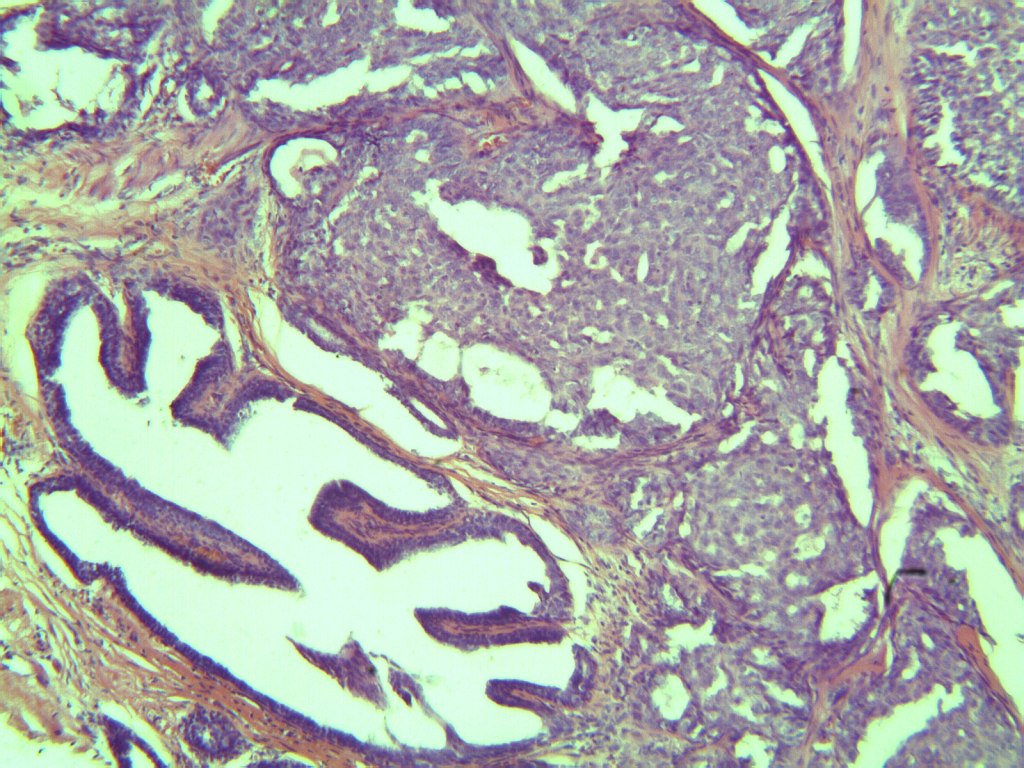

H&E Breast Slide H&E Breast Slide H&E Breast Slide

The nuclear pleomorphism and mitotic activity suggest Grade 2 invasive ductal carcinoma. Stromal invasion pattern is clear.

Findings align with Grade 2 invasive ductal carcinoma. Stromal invasion is evident; ER/PR/HER2 testing is recommended.

H&E Breast Slide

Breast H&E